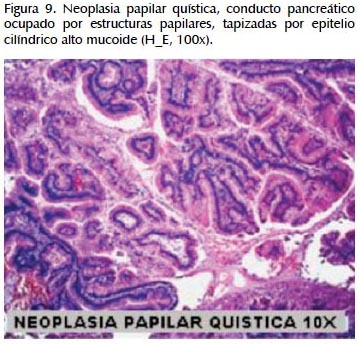

La alteración fundamental en este caso es la presencia de marcada dilatación de los conductos pancreáticos (Figuras 6, 7, 8, 9, 10 y 11) con variable hiperplasia de los conductos menores periféricos.

Los quistes están limitados por células ductales altas, algunas mucinosas, en su mayor extensión dispuestas en una fila. De manera focal se ve proyecciones papilares del epitelio y también focos de erosión con reacción inflamatoria, exudado linfocitario y formación de tejido de granulación.

El resto del parénquima pancreático muestra múltiples focos de autolisis y variable hiperplasia de los ductos.